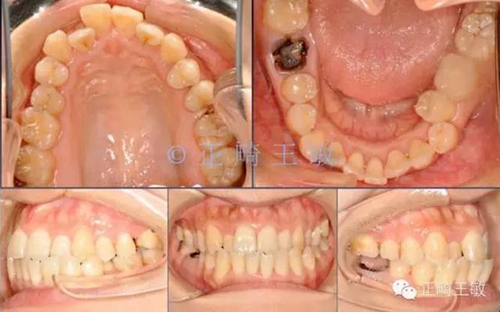

10.jpg

一年后復(fù)查,沒有任何問題。

11.jpg

只拔了一顆小牙,解決了大問題。